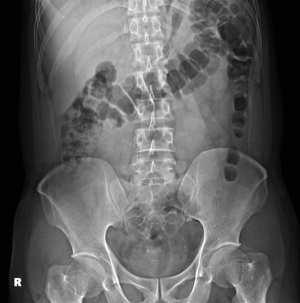

A 42-year-old male arrived at the ED in MacKay Memorial Hospital, Taipei, seeking assistance for the removal of a wooden object retained in his rectum. He admitted to inserting the object, described as a Y-shaped wooden massager typically used for shoulder and neck massage, for sexual stimulation approximately 8 hours prior to his ED visit. The object measured approximately 10 cm × 4.5 cm and weighed 35 g, as per the product description on a shopping website. The patient denied experiencing fever, nausea, vomiting, abdominal pain, diarrhea, or bloody stool. Initial imaging with kidney-ureter-bladder (KUB) X-ray revealed only nonspecific findings of bowel gas and stool collection (Figure 1). All procedures performed in this study were in accordance with the ethical standards of the institutional and/or national research committee(s) and with the Declaration of Helsinki and its subsequent amendments. Written informed consent was obtained from the patient for publication of this article and accompanying images. A copy of the written consent is available for review by the editorial office of this journal.